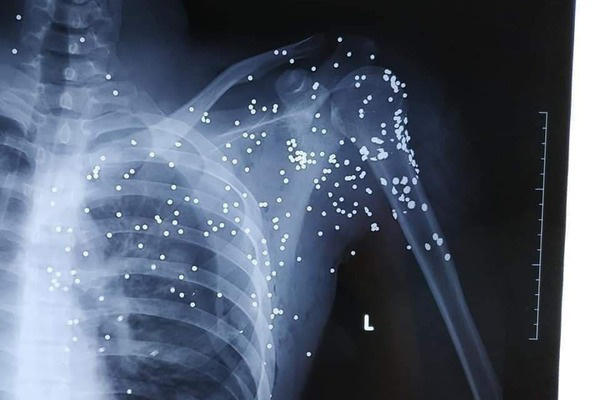

Kết quả chụp X.Quang cho thấy, anh Bùi Huy Hoàng bị nhiều mảnh đạn găm tại vùng cổ, vai trái và phía trên ngực trái, mất nhiều máu.

Ảnh chụp X-Quang cho thấy các mảnh đạn đang găm trên cơ thể.

Dựa trên tình hình của nạn nhân, cụ thể là các vết đạn xuất hiện dày đặc nơi vùng phổi của nạn nhân nên phía Bệnh viện Đa khoa tỉnh Thái Bình đã chuyển bệnh nhân lên cấp cứu tại Bệnh viện Hữu nghị Việt Đức, TP Hà Nội.